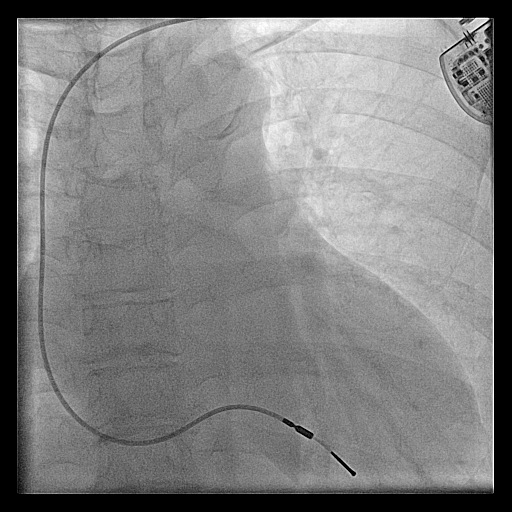

Confirm venous position

wires_ivc.jpg